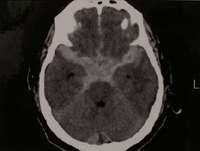

脳は外側から硬膜、くも膜、軟膜で覆われており、くも膜と軟膜のすき間はくも膜下腔と呼ばれています。このくも膜下腔に出血を起こした状態がくも膜下出血です。

原因としては脳動脈の一部がふくらんでできた動脈瘤 (どうみゃくりゅう)の破裂によるものが大部分です。男性より女性に多く、40歳以降に多くみられ、年齢とともに増加します。家系内に動脈瘤やくも膜下出血の方がいるときは発生頻度が高く、また高血圧、喫煙、過度の飲酒は動脈瘤破裂の可能性を数倍高くするという報告もあります。